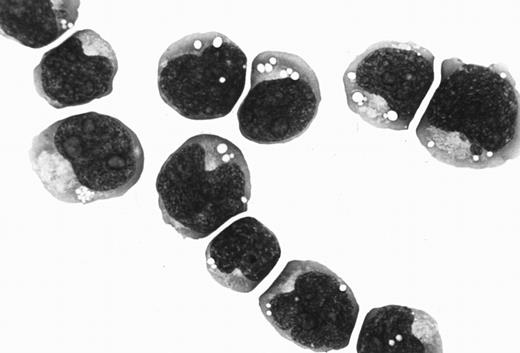

Case history and establishment of cell line.The Katata line was established from a 58-year-old Japanese woman who was referred to our hospital for a growing mass in the epigastric region. On physical examination, a firm nodule, 2 cm in diameter, was also found in her right breast. A diagnosis of Burkitt's lymphoma was made on a biopsy specimen of the breast tumor (Fig 1). Karyotype analysis of the tumor sample disclosed several chromosomal abnormalities including t(8; 14)(q24; q32). Gastric endoscopy revealed tumorous involvement of the stomach. A bone marrow (BM) aspirate showed infiltration of lymphoma cells with an L3 morphology (French-American-British classification) that amounted to 42.3% of the nucleated cells. The patient was treated with two courses of combination chemotherapy of cyclophosphamide, adriamycin, vincristine, and prednisolone, but the chemotherapeutic response was minimal. The disease progressed into a leukemic phase and she died of septicemia 6 weeks after admission. Serological titers for EBV were as follows: antiviral capsid antigen (VCA) IgG, 1:40; anti-VCA IgM, <1:10; anti-VCA IgA, <1:10; antiearly antigen IgG, <1:10; and antinuclear antigen, <1:10. The anti-HHV-6 antibody was not tested.

(A) Histology of the original biopsy specimen from the breast tumor, showing Burkitt's lymphoma with starry-sky appearance. Hematoxylin and eosin stain (original magnification [OM] × 400). (B) Imprint smear of the tumor, showing lymphoma cells with vacuolated cytoplasm, generally round nuclei, and prominent nucleoli. May-Grünwald-Giemsa stain (OM × 1,000).

Morphology, phenotype, and genotype.The Katata line was predominantly composed of medium-sized cells with round or slightly irregular nuclei and one or more prominent nucleoli. The cytoplasm was basophilic and contained prominent vacuoles (Fig 2). The morphology of Katata cells closely resembled the original lymphoma cells. The results of cell marker analysis of the patient's lymphoma cells and cell line are summarized in Table 1. Both original lymphoma cells and cell line displayed an immunophenotype of immature B cells with a positive reactivity for CD19 and CD20, as well as CD10, but without expression of surface and cytoplasmic Ig. They did not express T-cell and myeloid differentiation antigens. Chromosomal analyses of the cell line were performed on two separate occasions at the earlier passage and over 50th passage. On both occasions, the t(8:14)(q24:q32) translocation was observed in all metaphases analyzed.